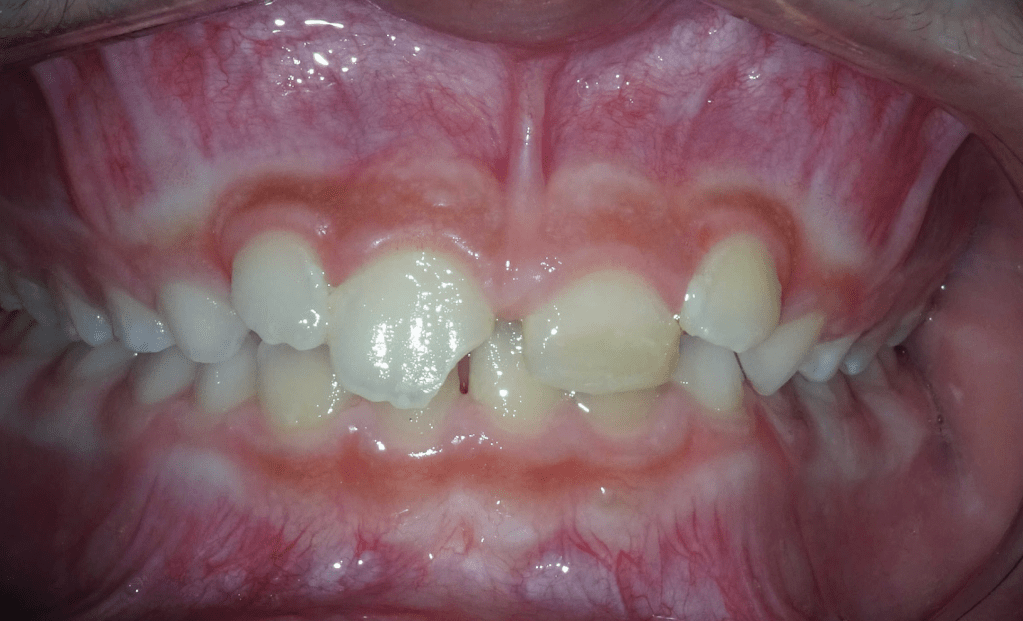

Endodoncia diente temporal, ausencia definitivo

Pulpotomías

Pulpotomía diente temporal